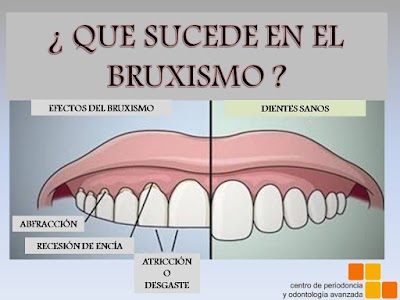

Mc Periodontal | Periodoncista Monterrey - Dentista | Dra. Maria Cristina Garcia